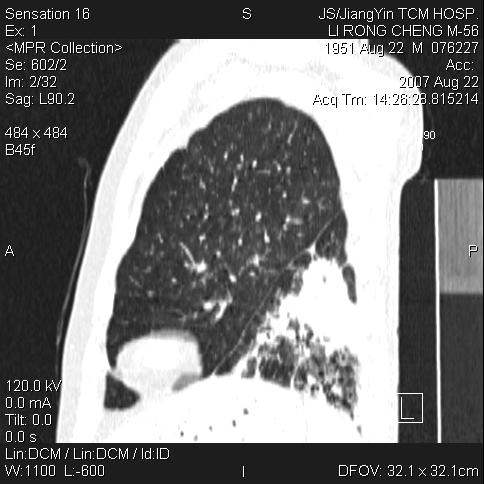

标题: CT9479:M,56Y,DM病史,咳嗽发热5天.肺脓疡.肺癌? [打印本页]

边灶边缘较光整,冠状位病灶呈大片状,,内有空洞,有胸膜反应,但无明显胸膜外侵犯征像,结合病史支持考虑肺肿脓,不排除结核,治疗后复查

好多钙化灶哦,病灶位于下叶背段,或许考虑结核更合适,做下相应检查先

考虑结核病播散!

1:病灶不是实质肿块形态,胸膜脂肪间隙存在!

2:周围有卫星病灶,不象阻塞性肺炎

3:往下间质增厚,播散征象.

左肺下叶支气管呈小囊状扩张。下叶背段有类圆形高密度影,边缘模糊,外与胸膜相连。左侧胸膜增厚粘连。心包膜增厚。结合病史考虑1支扩并感染2胸膜及心包炎。

左下肺团片状类软组织密度影,形态不规则,边缘欠规整,其内可见液化区及气体影,病灶内侧见引流支气管影,相邻胸膜反应性增厚。病灶周围肺野内见增粗支气管,壁厚,边缘模糊。考虑:支气管扩张并感染;肺脓肿。